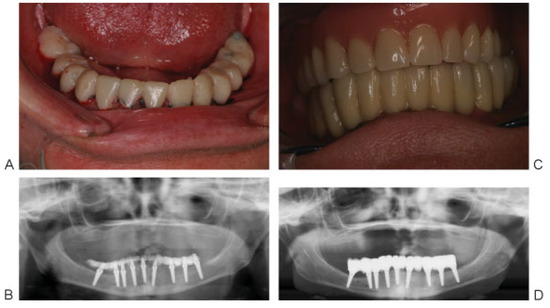

Clinical Report

Figure 1. Severely resorbed bilateral posterior edentulous mandible and periodontal disease and calculus on the remaining teeth.

Figure 2. Preoperative orthopantomogram showing atrophic posterior mandible.

Cmtr 07 00014 g002